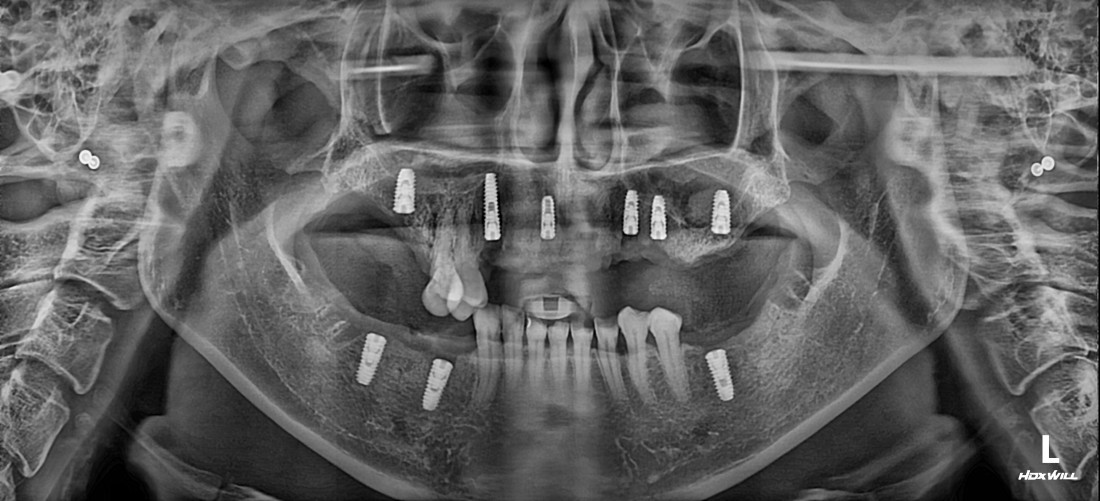

광주 상악임플란트 치과는

전체 임플란트 수술도

단 2번의 수술만으로

완성합니다.

광주 상악임플란트 치과에서는

위 / 아래 전체 임플란트를

붓기, 출혈, 통증을 최소화할 수 있는

디지털 가이드 임플란트 수술방법으로

단 2번의 수술만으로 완성하고 있습니다.